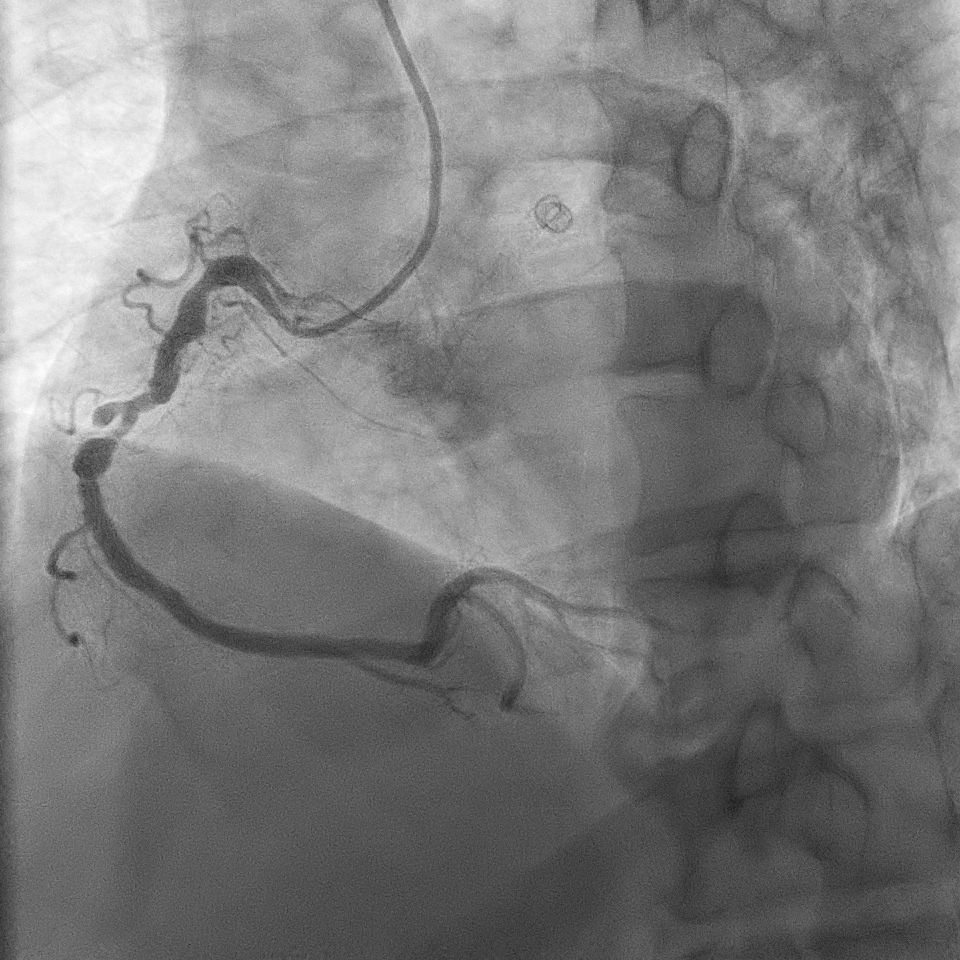

A right radial artery approach with 6Fr sheath was used. The right coronary system was engaged with 6Fr Judkin Right (JR4) guiding catheter. The posterior left ventricular branch was wired with Runthrough NS. Intravascular ultrasound (IVUS) showed distal RCA landing zone vessel size of 4.0-4.5mm in diameter. The mid RCA showed minimal luminal area (MLA) of 1.95mm2 with fibrous plaque and calcification at 12 o'clock. The proximal RCA landing vessel size was 4.5-5.0mm in diameter. The lesion was predilated with NC Trek Neo balloon 3.0x15mm. Attempted multiple times to deliver the stent SYNERGY 4.0X48mm but failed. The stent could not be passed into proximal RCA and eventually the distal stent edge crimpled and unable to be withdrawn into the guiding catheter. Tried to pull back system enbloc into the radial artery. Attempted to pull the stent into guider but failed again. The guiding catheter was removed. The stent was left with coronary wire in situ. Exchanged 6Fr radial sheath to slender sheath and attempted to snare stent with 2.0mm snare but failed. Attempted multiple wire wrapping technique with 3 BMW wires but failed. Decided to puncture right femoral artery with 8Fr sheath. A 7Fr JR4 guiding catheter was introduced into right brachial artery. A 7mm snare then snared the stent and removed it via femoral. The lesion was predilated with Scoreflex 3.5x20mm, stented with Supraflex Cruz 4.0x48mm and post-dilated with NC balloon 4.5mm. Result was TIMI 3 and no dissection.

Case Summary